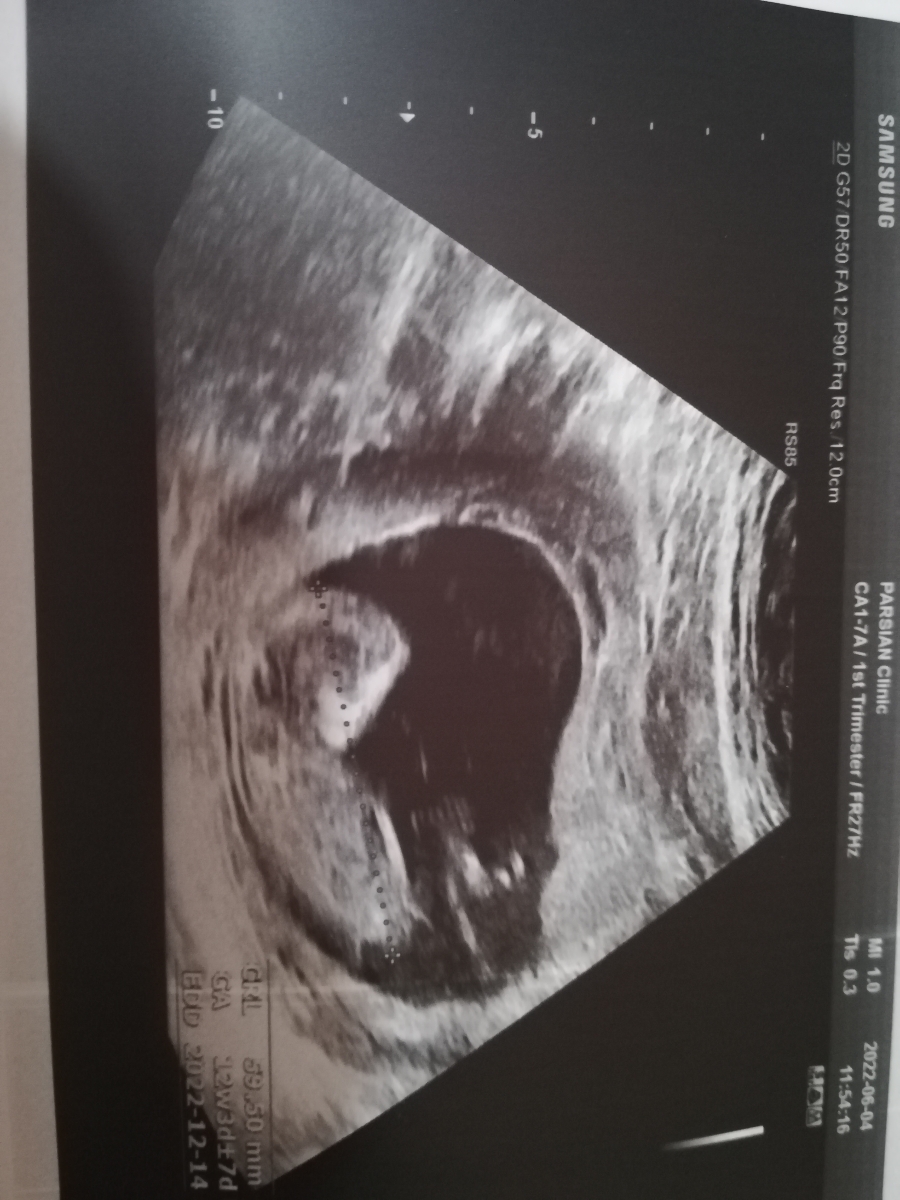

سونو NT انجام دادم میشه برا منم حدس بزنید نی نی چیه؟ دکترم احتمال داد بعدش میگم

طول سرویس 32 کم نیس

سونو شکمی گرفتن

نه عزیزم خوبه ،تا ۳۰ باشه اوکیه